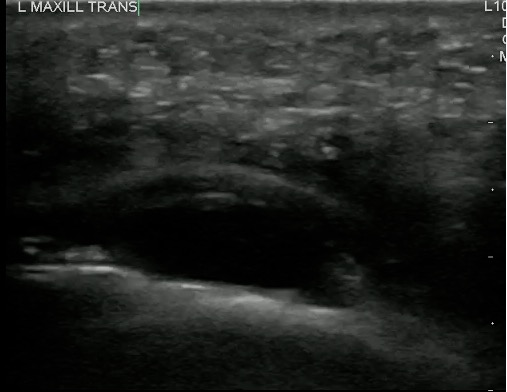

- Figure 5 and 6. Normal Mandible

- Bony structures like mandible, maxilla appear hyperechoic with a posterior hypoechoic acoustic shadow underneath.

- Fat has hyperechoic appearance on ultrasound.

- Muscles are generally visualized as hypoechoic structures but have a more heterogeneous striated appearance.

- Normal Mandible:

-

Video 4. Normal Mandible